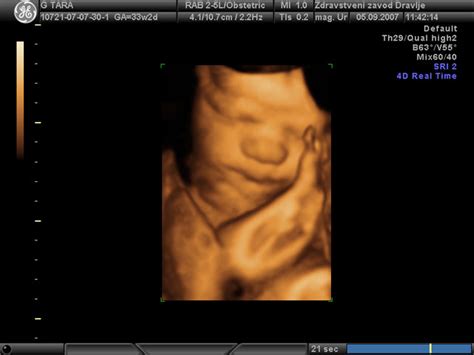

Pri 28. tednu plod že zaznava svetlobo skozi maternico, pogosto utripa z očmi in njegovi možgani razvijajo milijarde nevronov. V tem obdobju so pomembni redni ginekološki pregledi, ki vključujejo merjenje rasti plodu z ultrazvokom, oceno količine plodovnice, izgled posteljice in preverjanje pretokov skozi žile.